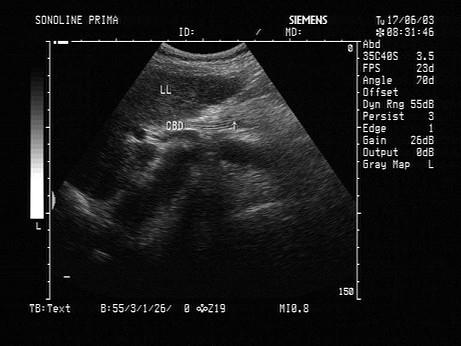

女,27岁,上腹部剧烈疼痛2天。声像图如图所示,诊断为?(?)A.胆道蛔虫B.胆道结石C.胆道胆汁淤积D.引流管回声E.胆管癌

问题 女,27岁,上腹部剧烈疼痛2天。声像图如图所示,诊断为?(?)

选项 A.胆道蛔虫 B.胆道结石 C.胆道胆汁淤积 D.引流管回声 E.胆管癌

答案 A